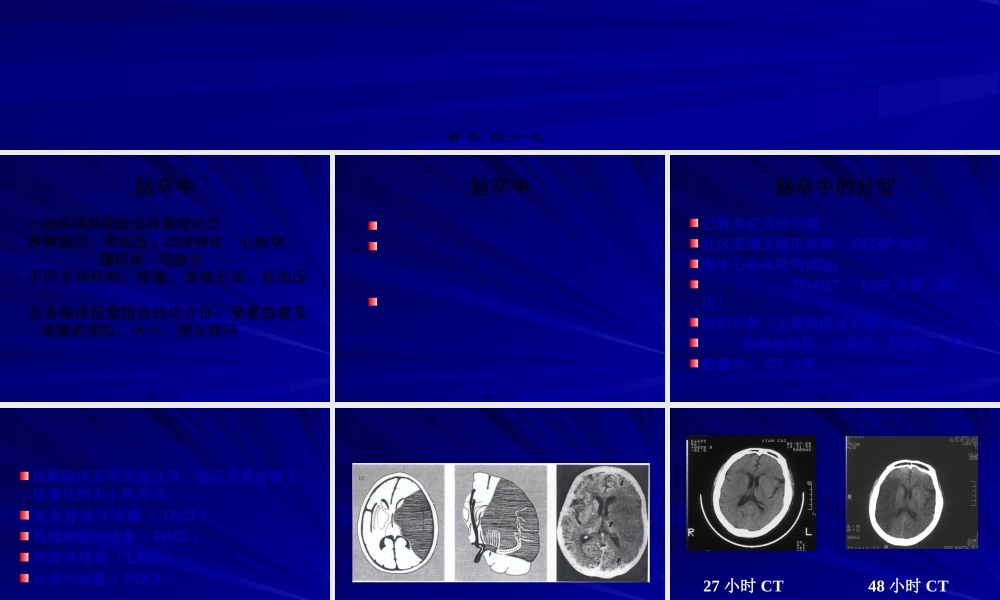

缺血性卒中分型第一页,共三十一页。脑卒中一组疾病共同的临床病理状态多种病因:高血压、动脉硬化、心脏病、糖尿病、动脉炎┄不同发病机制:栓塞、血栓形成、低血压┄众多临床征象组合的综合征:受累血管及堵塞的部位、大小、侧支循环第二页,共三十一页。脑卒中第三页,共三十一页。脑卒中的分型已较多应用的分型社区流调及临床观察:OCSP分型多中心临床药物试验:TOAST、LSR分型〔病因〕临床诊断〔主要病因及机制〕:动脉血栓性、心源性、腔隙性、其他影像学:CT分型第四页,共三十一页。依据临床表现迅速分型,提示受累血管及堵塞灶的大小和部位:完全前循环堵塞〔TACI〕局部前循环堵塞〔PACI〕腔隙性堵塞〔LACI〕后循环堵塞〔POCI〕第五页,共三十一页。TACI第六页,共三十一页。27小时CT48小时CTTACI第七页,共三十一页。PACI-皮层梗塞第八页,共三十一页。PACI-基底节梗塞第九页,共三十一页。LACI-腔隙性梗塞第十页,共三十一页。POCI-小脑和脑桥梗塞第十一页,共三十一页。POCI--中脑堵塞第十二页,共三十一页。POCI-延髓梗塞第十三页,共三十一页。CT分型按解剖部位分为大脑堵塞、小脑堵塞及脑干堵塞,其中大脑堵塞又可分为:大堵塞:超过一个脑叶,5cm以上中堵塞:小于一个脑叶,3.1~5cm小堵塞:1.6~3cm腔隙堵塞:1.5cm以下多发性堵塞:多个中、小及腔隙堵塞第十四页,共三十一页。大梗塞中梗塞第十五页,共三十一页。小梗塞腔隙性梗塞第十六页,共三十一页。多发性梗塞第十七页,共三十一页。第十八页,共三十一页。心源性脑栓塞大动脉粥样硬化小动脉闭塞〔腔梗〕其他原因未能确定病因第十九页,共三十一页。多种可以产生心源性栓子的疾病引发的脑栓塞:卒中发作前4周内的心梗充血性心力衰竭冠状动脉狭窄房颤、房扑、病窦综合征人工心脏瓣膜心室壁运动不能和心室壁运动功能减退心房、心室、主动脉、冠状动脉血栓形成第二十页,共三十一页。心源性栓子的来源机械心脏瓣膜二尖瓣狭窄伴心房纤颤心房纤颤、病窦综合征4周之内的心梗左心房或左心耳、左心室血栓扩张型心肌病左心室区段性运动功能不良左心房粘液瘤感染性心内膜炎第二十一页,共三十一页。心源性栓子的来源二尖瓣脱垂、二尖瓣环状钙化二尖瓣狭窄不伴房颤房间隔缺损、卵圆孔未闭心房扑动、单独出现的房颤生物心脏瓣膜非细菌性血栓性心内膜炎充血性心力衰竭左心室区段性运动功能减退>4周,<6月的心梗第二十二页,共三十一页...